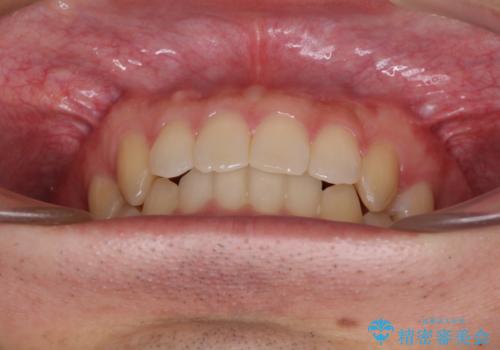

前歯の咬み合わせとデコボコを解消 インビザラインによる矯正治療

- 上下前歯のデコボコと深い咬み合わせを気にして来院された患者様です。

インビザラインによる上下歯列の拡大と、IPR(歯と歯の間を削る)にるスペースの獲得により、前歯のデコボコとディープバイトを改善することとしました。

もう少し下の前歯を整えたかったのですが、患者様の治療を早く終了させたいという希望により、細かい叢生を残しての終了となりました。